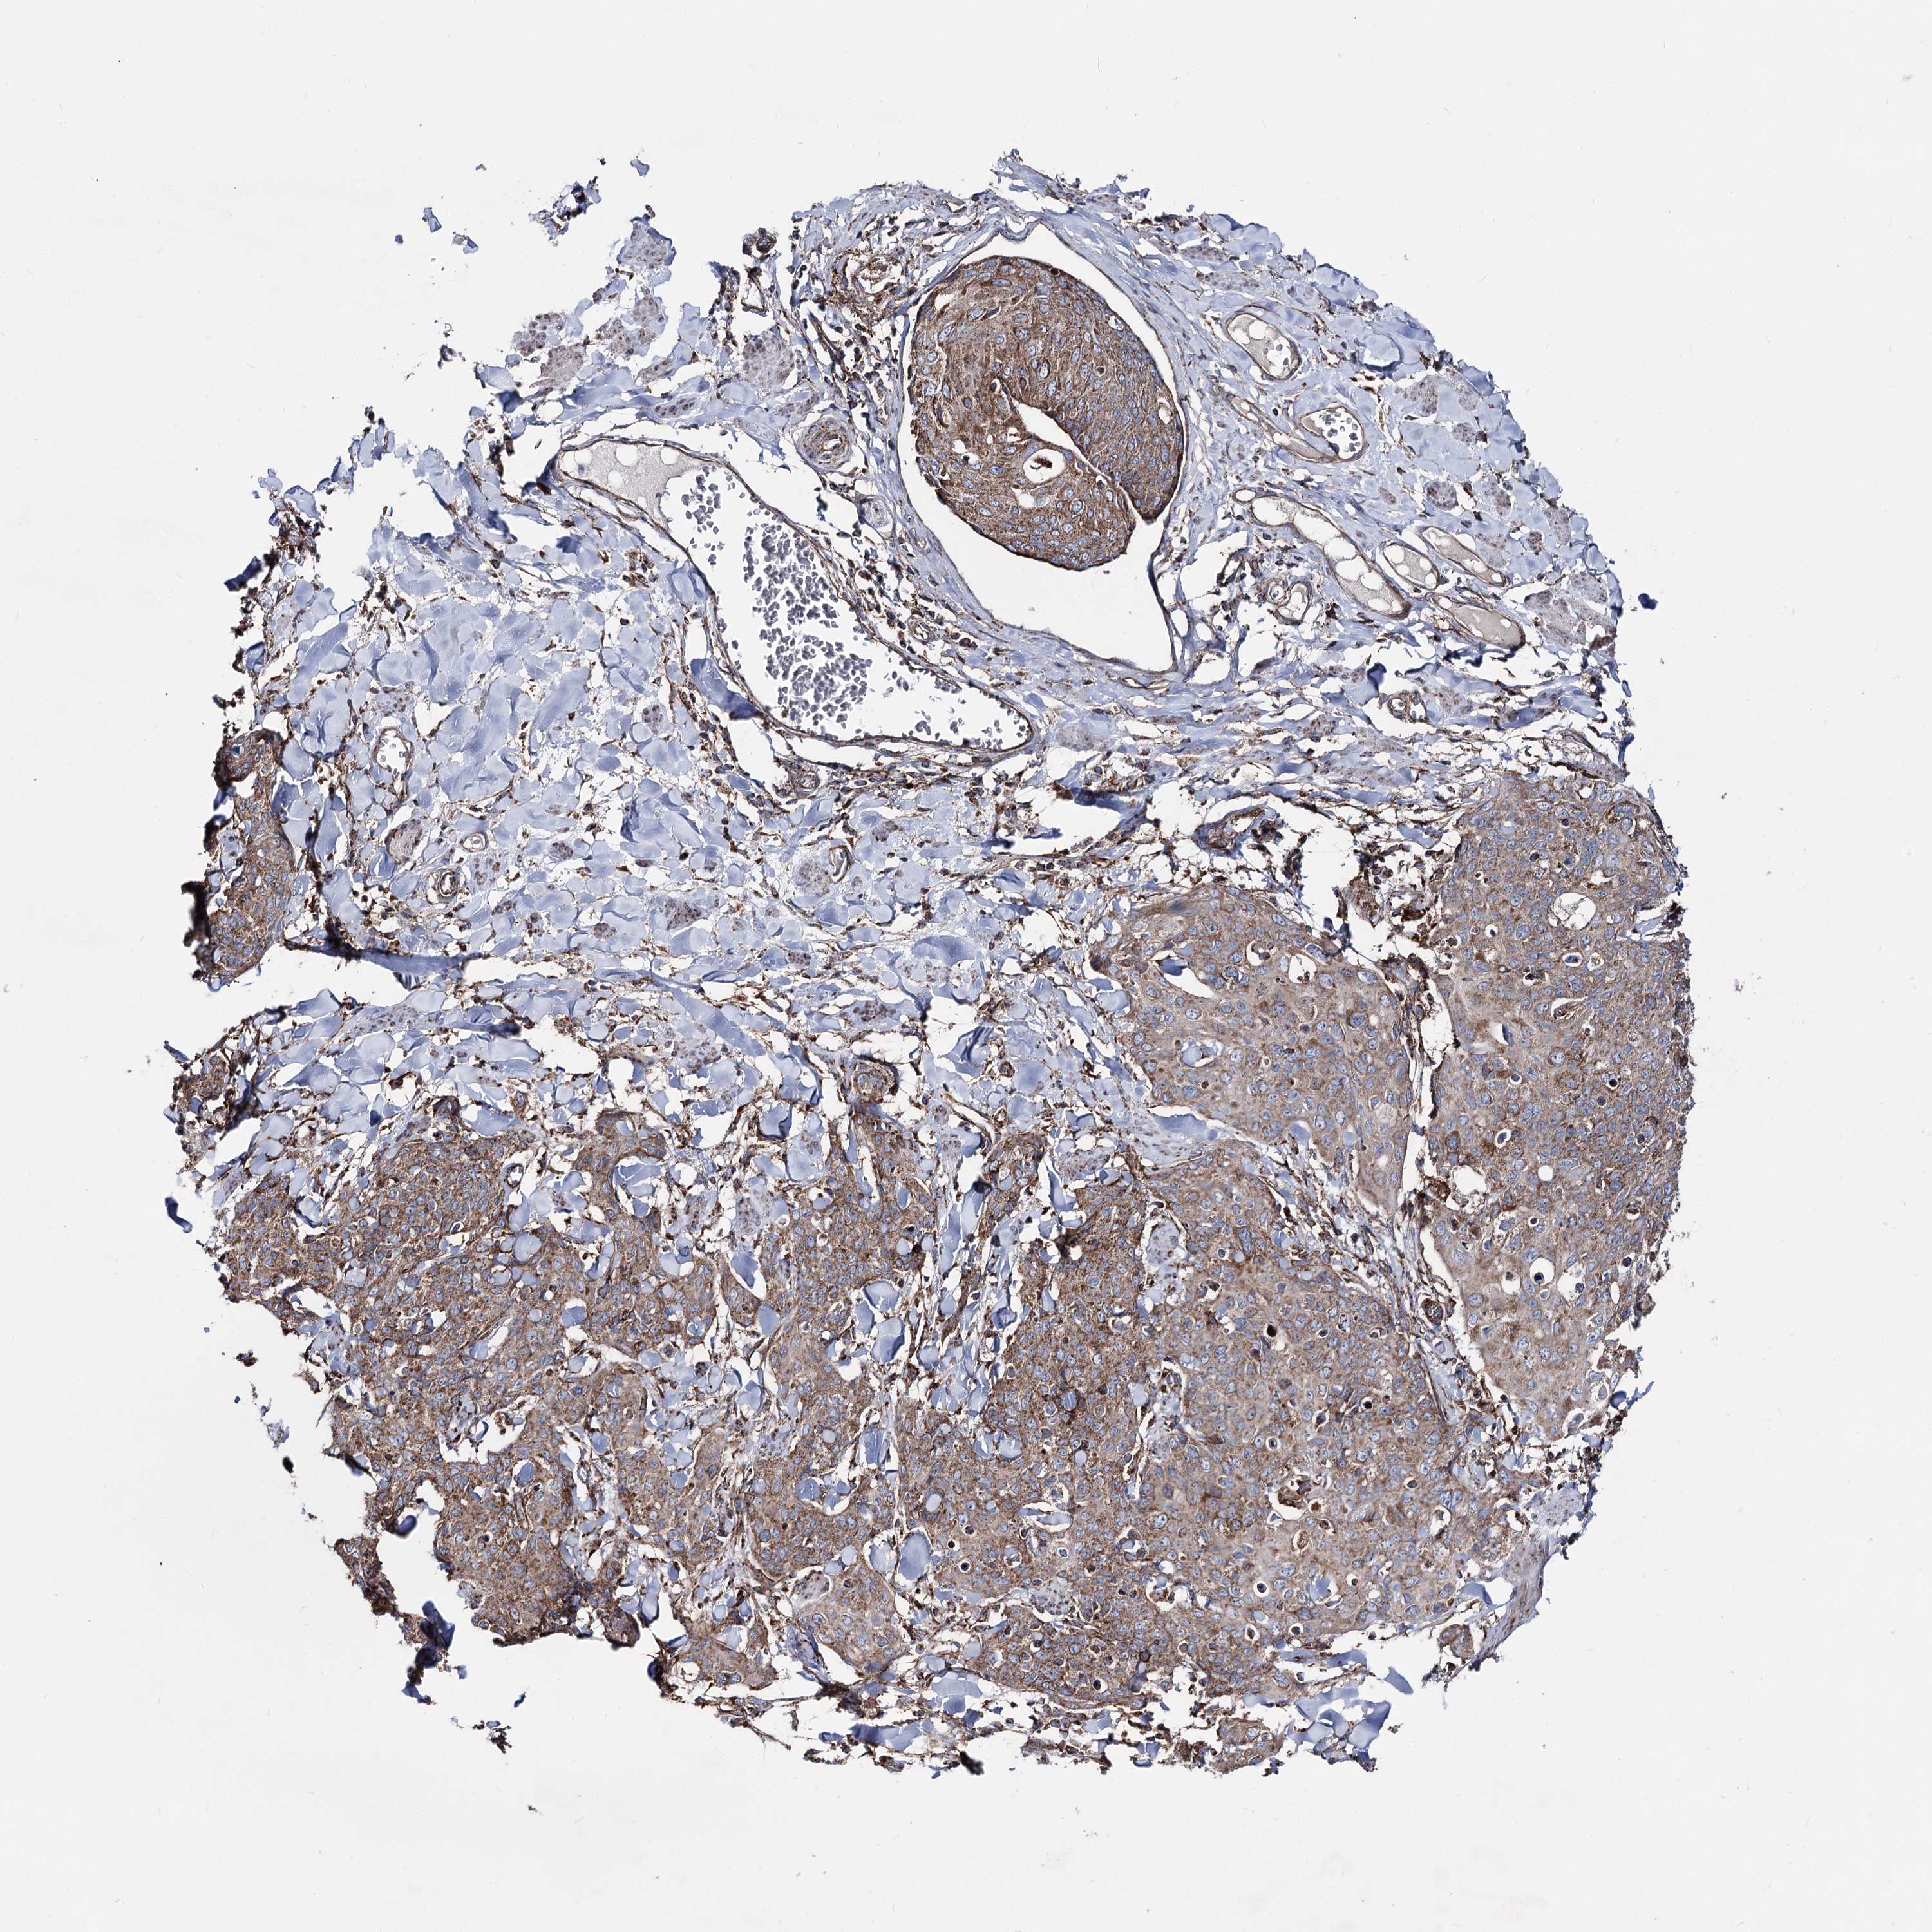

Basal cell and squamous cell cancer

SKIN CANCER - Protein expressioni

A mouse-over function shows sample information and annotation data. Click on an image to view it in a full screen mode. Samples can be filtered based on level of antibody staining by selecting one or several of the following categories: high, medium, low and not detected. The assay and annotation is described here.

Each image is clickable and will lead to virtual microscopy that enables deeper exploration of all samples and also displays staining intensity scores, fraction scores and subcellular localization as well as patient and tissue information for each sample.

Antibody HPA038694

Antibody HPA038695

Squamous cell carcinoma, metastatic, NOS